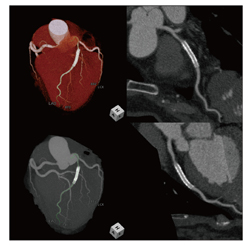

(3)肝臓評価、冠動脈評価、下肢血 管評価

そのほか、琉球大学医学部附属病院を含めた他院からの依頼で、肝切除術の術前のボリュームメトリーや血管抽出を行っている(図3)。また、256列のiCTが導入後は、心臓検査件数が急増しziostation2では,その処理をすべて行っている。井戸主任は「ziostation2になって冠動脈解析の精度が向上し、冠動脈の抽出が速く正確に行えるようになりました。iCTの導入と合わせて迅速に精度の高い検査が行えます」と心臓CTでのメリットを語る(図4)。

図3 肝切除術前の肝臓評価 |

図4 冠動脈解析 |